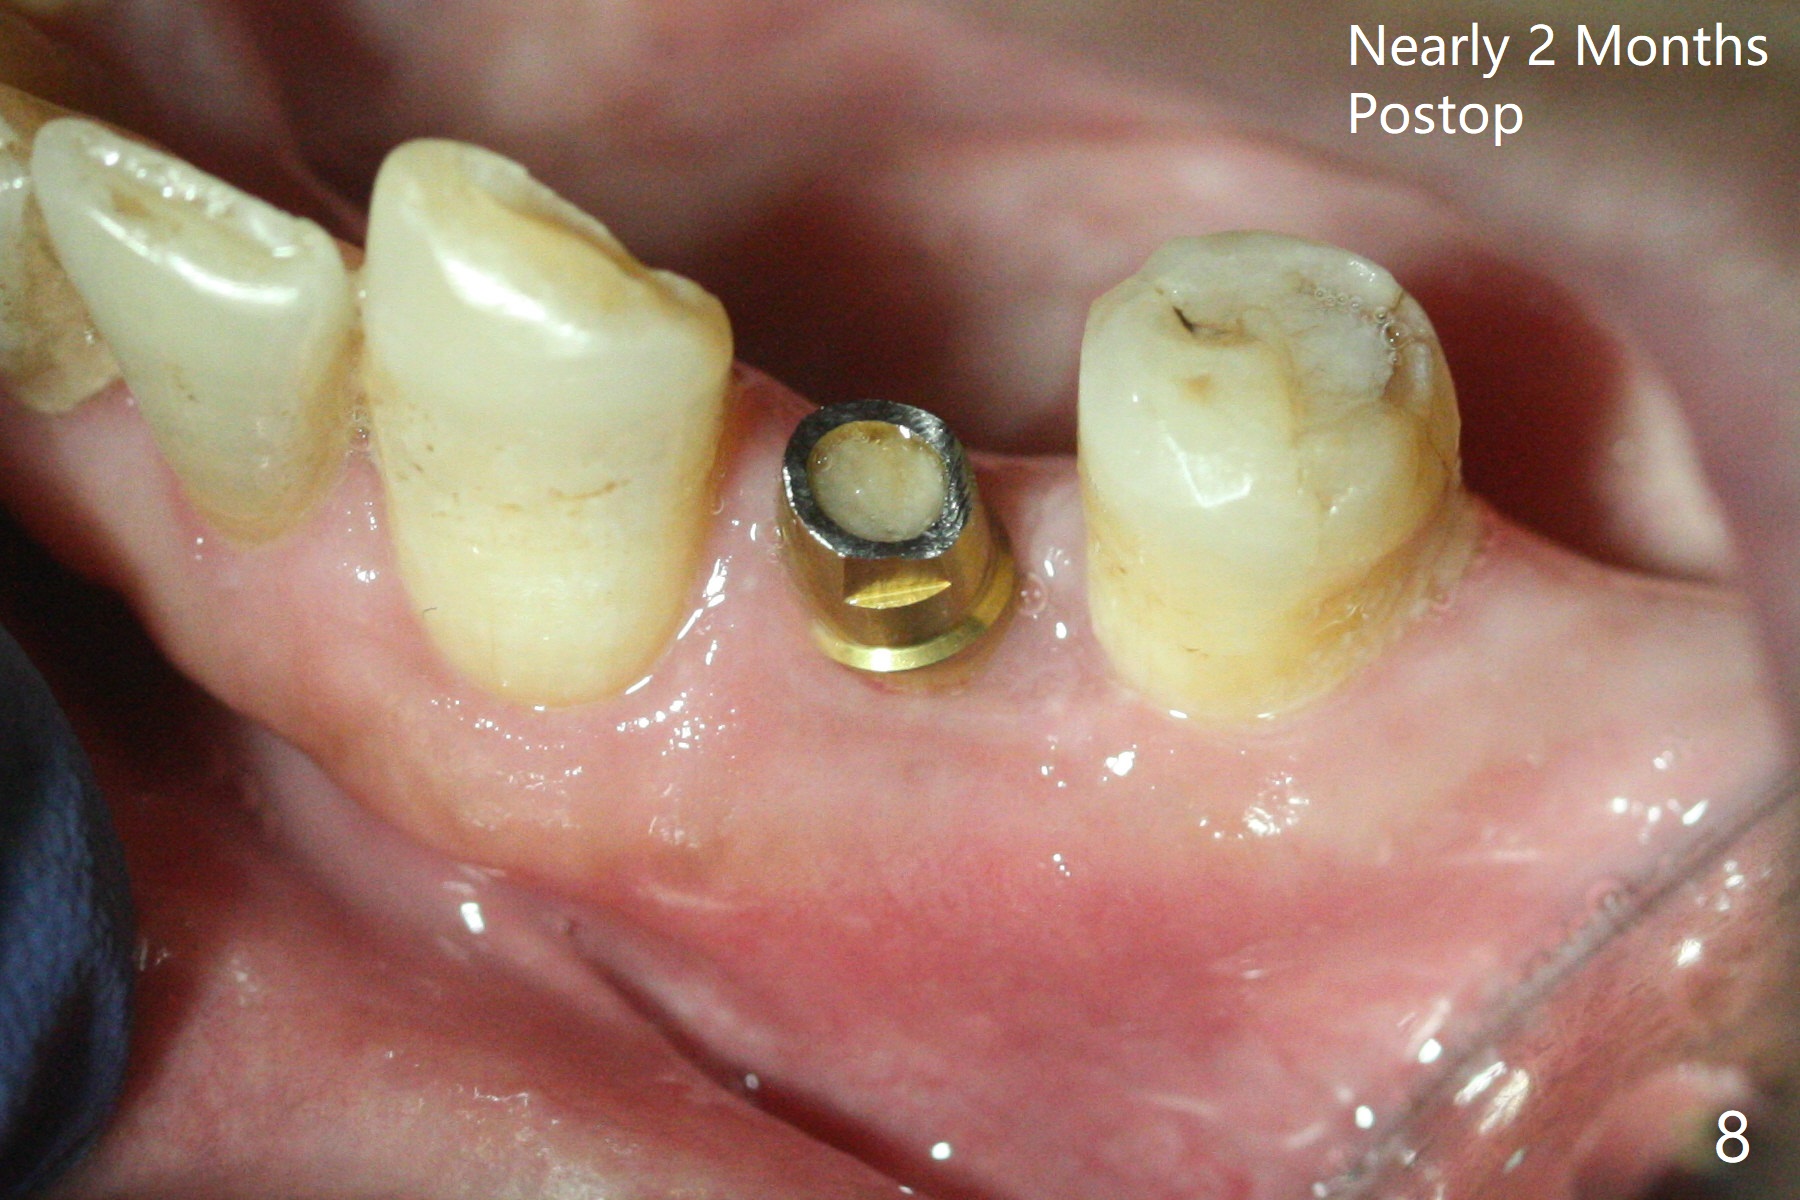

Since the root surface at #29 is distinct (Fig.1), while that at #21 is not (with subgingival caries, Fig.2), closed and open socket shields are done at #29 and 21, respectively (Fig.3,4 S), followed by implant placement with guide (Fig.4-6). With socket shield, there is limited remaining space for bone graft (Fig.4). The shield associated with the closed technique is exposed nearly 2 months postop (Fig.7), while the one associated with the open technique is not (Fig.8). The buccal plate is minimally atrophic with either technique.